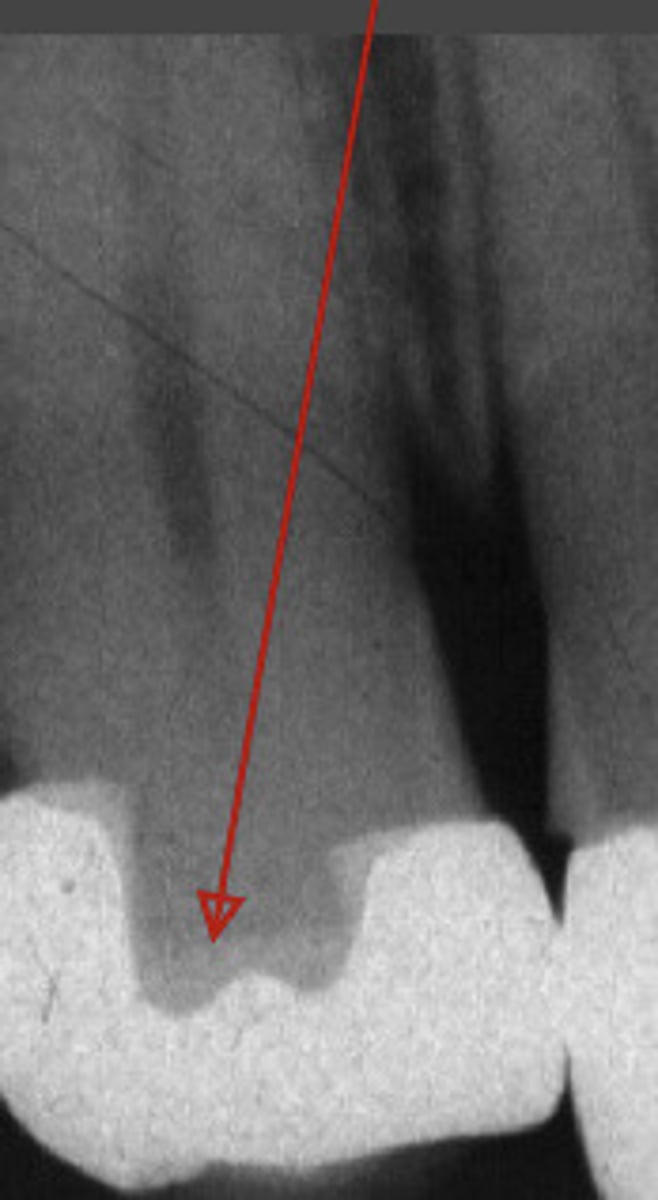

overhang